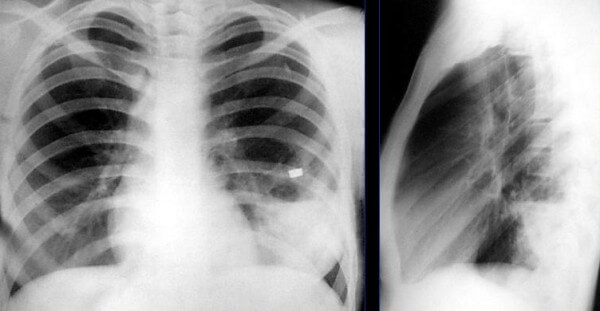

На снимке видны отдельные небольшие очаги поражения ( 1-1,5 см), расположенные в одном из легких (при билатеральной форме – в обоих). Заметным в данном случае будет расширение корней легких из-за наполнения жидким экссудатом.

Снимок при очаговой пневмонии

Сегментарная пневмония – воспаляется целый сегмент легкого. Данная форма пневмонии может осложниться ателектазом (спадением части легкого с полной потерей его воздушности. Сегментарная форма воспаления может быть проявлением длительной затяжной пневмонии, переходящей в легочный фиброз или осложненной локальным хроническим бронхитом. На рентген-снимках виден целый сегмент, пораженный воспалением.

Снимок при сегментарной пневмонии